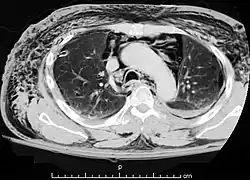

Zespół Hammana – spontanicznie powstała odma podskórna[1] i odma śródpiersia, które czasami wiążą się z wystąpieniem bólu. Występuje najczęściej u młodych kobiet[2].